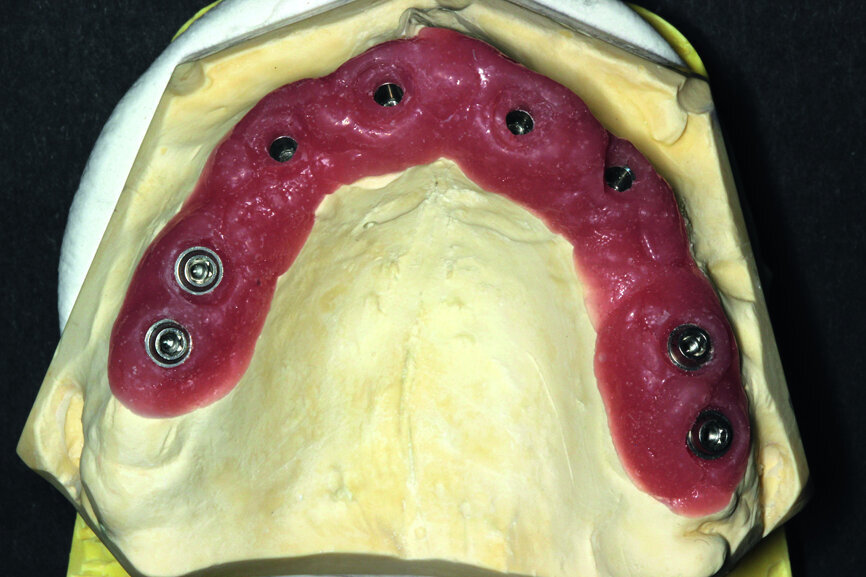

Fig. 10: Ready-made project of the supra-structure visible from the intragingival side.

Fig. 11: Suprastructure cut out and transferred onto the model.